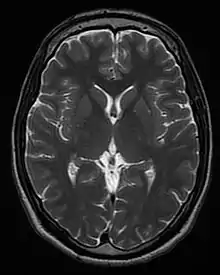

| T2 weighted | T2 | Measuring spin–spin relaxation by using long TR and TE times |

Standard foundation and comparison for other sequences |

![]() | |

Each tissue returns to its equilibrium state after excitation by the independent relaxation processes of T1 (spin-lattice; that is, magnetization in the same direction as the static magnetic field) and T2 (spin-spin; transverse to the static magnetic field). To create a T1-weighted image, magnetization is allowed to recover before measuring the MR signal by changing the repetition time (TR). This image weighting is useful for assessing the cerebral cortex, identifying fatty tissue, characterizing focal liver lesions, and in general, obtaining morphological information, as well as for post-contrast imaging. To create a T2-weighted image, magnetization is allowed to decay before measuring the MR signal by changing the echo time (TE). This image weighting is useful for detecting edema and inflammation, revealing white matter lesions, and assessing zonal anatomy in the prostate and uterus.